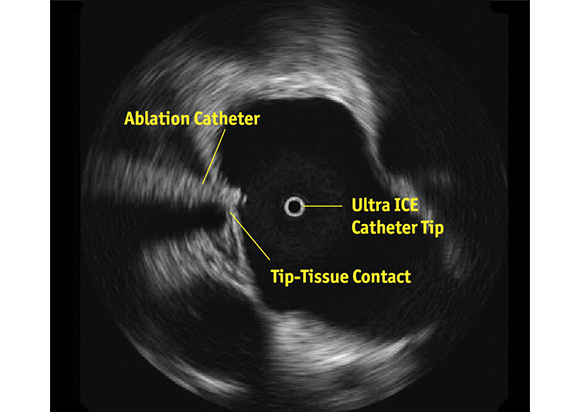

A key application for the ULTRA ICE PLUS catheter involves crossing the septum and then monitoring and helping to guide left-sided procedures. In this setting, ULTRA ICE PLUS catheter is designed to allow the user to:

• Visualize left atrial anatomy

• Confirm catheter location relative to the anatomy

• Verify tip-to-tissue contact

• Identify location of the esophagus relative to the ablation catheter

• Characterize acute lesion morphology: swelling, dimpling, and crater formation

• Monitor for any early signs of thrombus formation, stenosis, or pericardial effusion